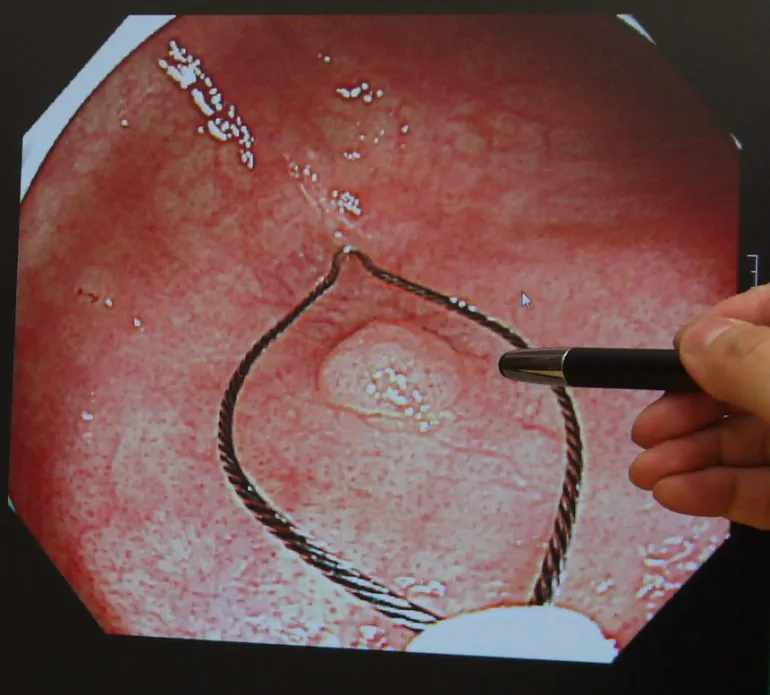

大腸カメラの症例